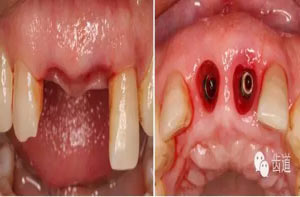

微創(chuàng)拔除根折牙

拔牙窩

探查唇側(cè)骨板(約齦下3-4mm)

半年后復(fù)診

半年后復(fù)診(牙齦袖口)